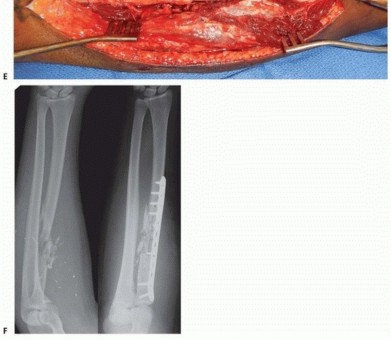

TECH FIG 1 • (continued) C. In the middle third, the radial artery (Rad. Art) and venae comitantes are identified exiting between brachioradialis (Br) and flexor carpi radialis (FCR). Light exsanguination assists in identifying vascular structures. The superficial radial nerve (SRN) is seen coursing between Br and FCR. D. The upper images demonstrate the pronator teres (P.T.) insertion on the radius. Middle image demonstrates drill hole placed through plate hole and radius for reattachment of P.T. (lower image). E. A segmental radius fracture and the AIN and vessel closely approximated to the proximal fragment. (continued)

TECH FIG 1 • (continued) F. Retraction of vessels with a Freer, allowing safe exposure of radius. G. Anatomic plate fixation of the segmental radius fracture with restoration of the radial bow.

TECH FIG 2 • (continued) D. The supinator has been partially divided to reveal the PIN coursing through its substance. The radial head is seen proximally and the radius fracture is seen distally. E. A 3.5-mm locking compression plate has been applied to the proximal radius. In this case, only two screws of proximal fixation were available, therefore locking screws were used. F. Pre and postoperative radiographs demonstrating bridge plating of this comminuted proximal radius fracture. A 3.5-mm locking plate was utilized. Proximally, the plate placement must be scrutinized to avoid impingement during forearm pronosupination. In our experience, this fracture is at significant risk for infection and nonunion. Acute bone grafting was not performed secondary to concern for infection.